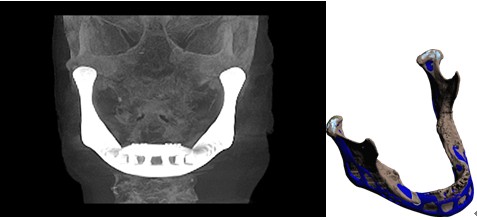

一位 83岁的老人由于患有慢性的骨头感染,因此换上了3D打印机“打印”出来的下颚骨,这是世界上首位使用3D打印产品做人体骨骼的案例。

6、定制化上颌骨替代物修复窦腺癌引起的骨缺损

某右上颌窦腺癌患者肿瘤切除手术后,面中1/3畸形并且复视明显。西安交通大学口腔医院根据病人的缺损形状与大小利用增材制造技术设计并制造了人工钛上颌骨。该替代物与病人的缺损区域配合良好,术后颜面畸形得以纠正,复视症状消失。